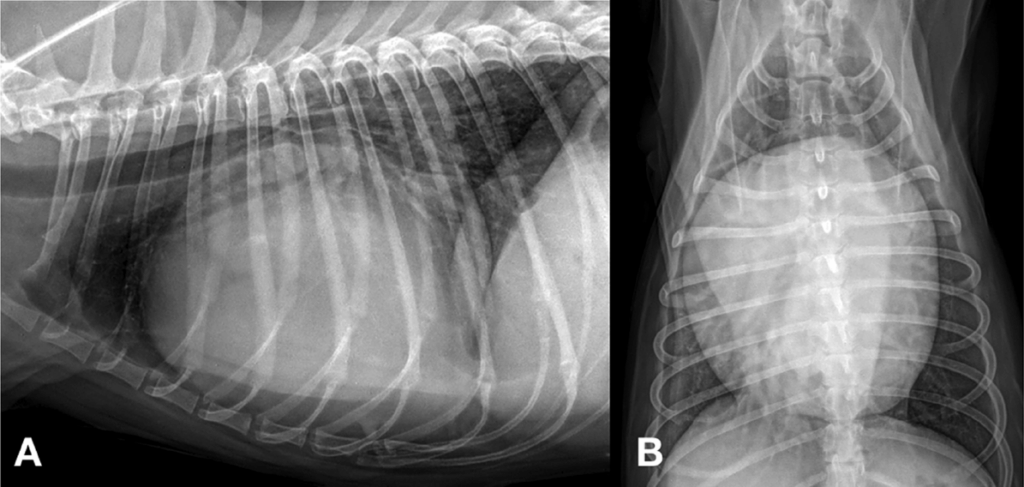

흉부 방사선 검사에서 심장이 전체적으로 매우 커져 있고, 둥근 모양을 보였습니다. 이러한 소견은 단순한 심장비대가 아니라, 심장을 둘러싼 공간에 액체가 차는 ‘심낭수’ 가능성을 시사합니다.

Fig 1. 현재 환자의 심낭수(pericardial effusion)가 확인된 초기 흉부 방사선 사진입니다.

A: 우측 측면 사진에서 심장이 심하게 커져 있으며, 둥근(globoid) 형태를 보이고 기관이 위로 들려 있습니다.

B: 배등 방향 사진에서 심장이 심하게 비대해 있고 둥근 형태를 보입니다.

(Initial thoracic radiography of the present patient with pericardial effusion.

A: The right lateral view shows severe cardiomegaly, a globoid-shaped heart, and tracheal elevation.

B: The ventrodorsal view shows severe cardiomegaly and a globoid-shaped heart.)